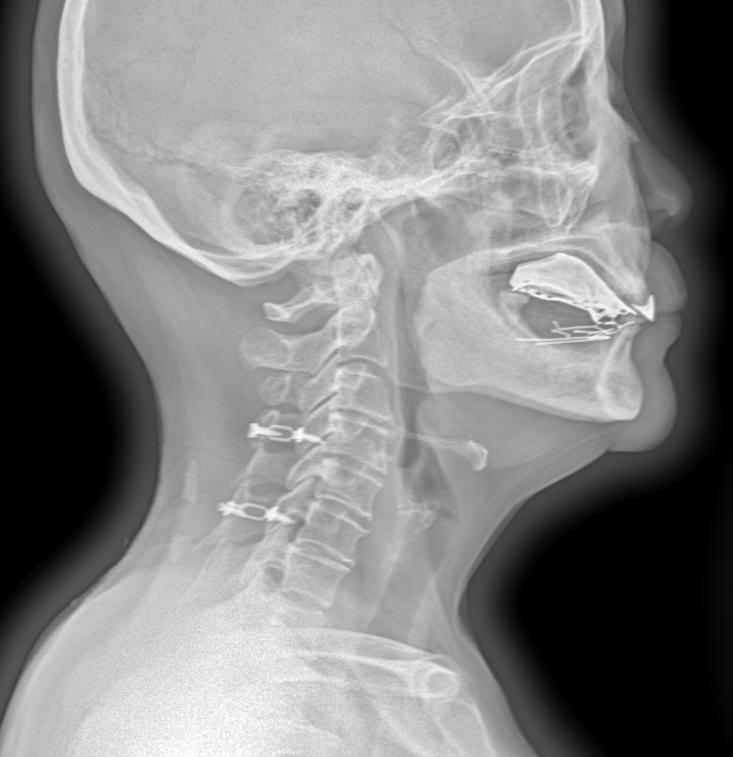

体征:车祸术后两年,颈椎疼痛就诊